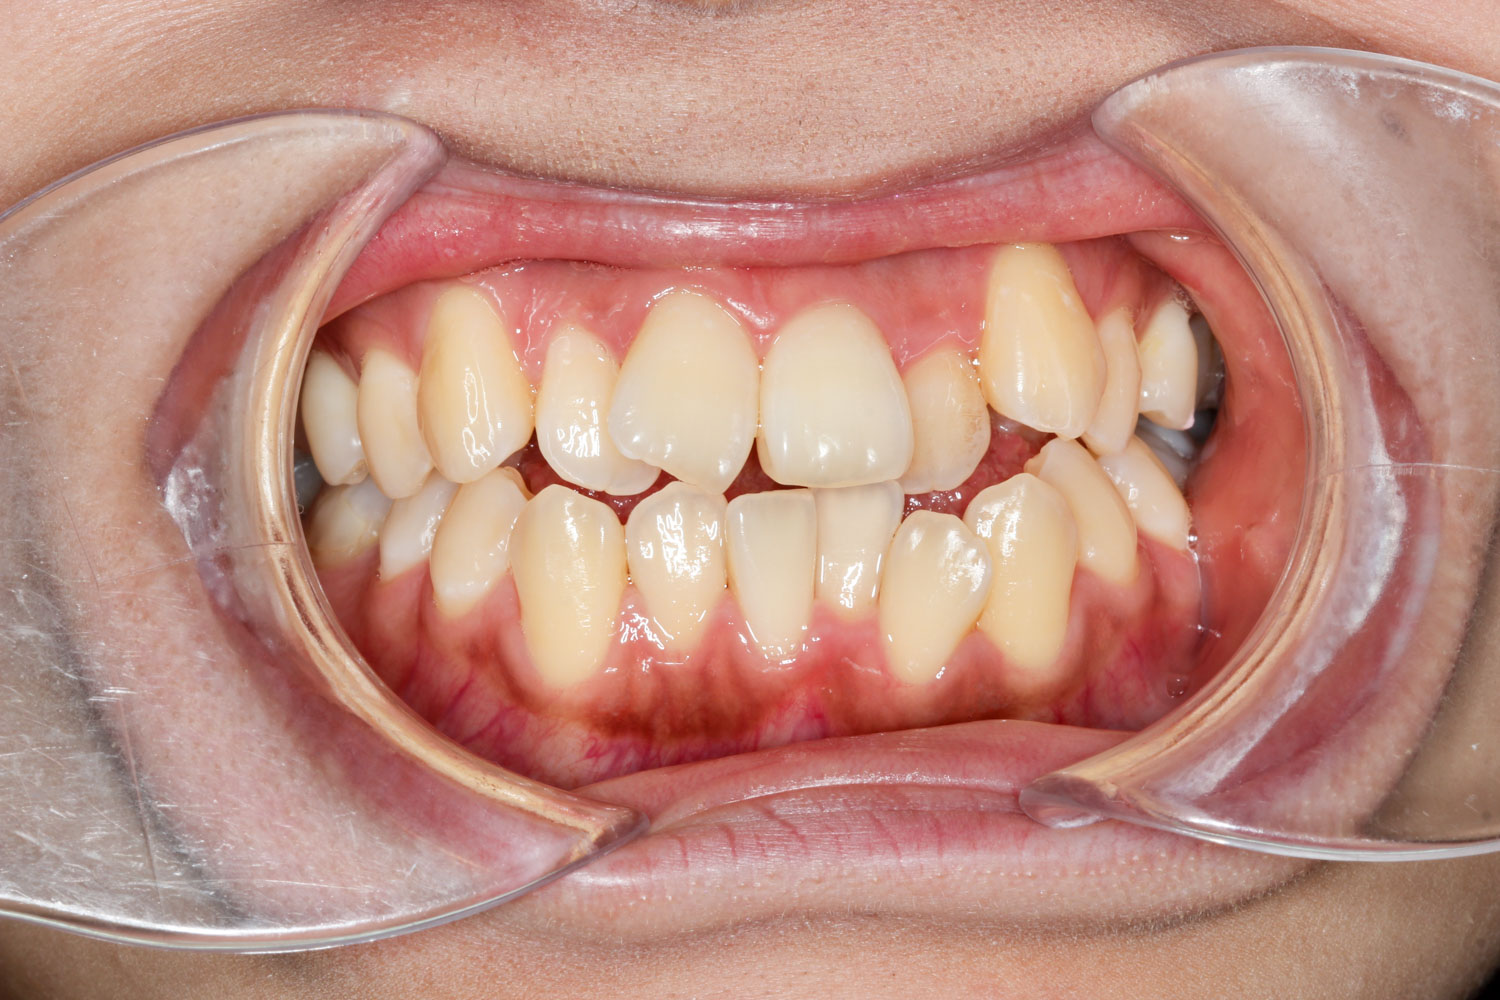

Before

年齢 10代

治療装置 上下とも裏側の矯正装置(フルリンガル)

治療内容 非抜歯

治療期間 2年8か月

リスク 歯の移動に伴う痛み、歯肉退縮、歯根吸収、歯肉炎、虫歯

主訴 八重歯が気になる

症状 叢生(ガタガタ)

治療回数 35回程度

総額費用 140万円程度